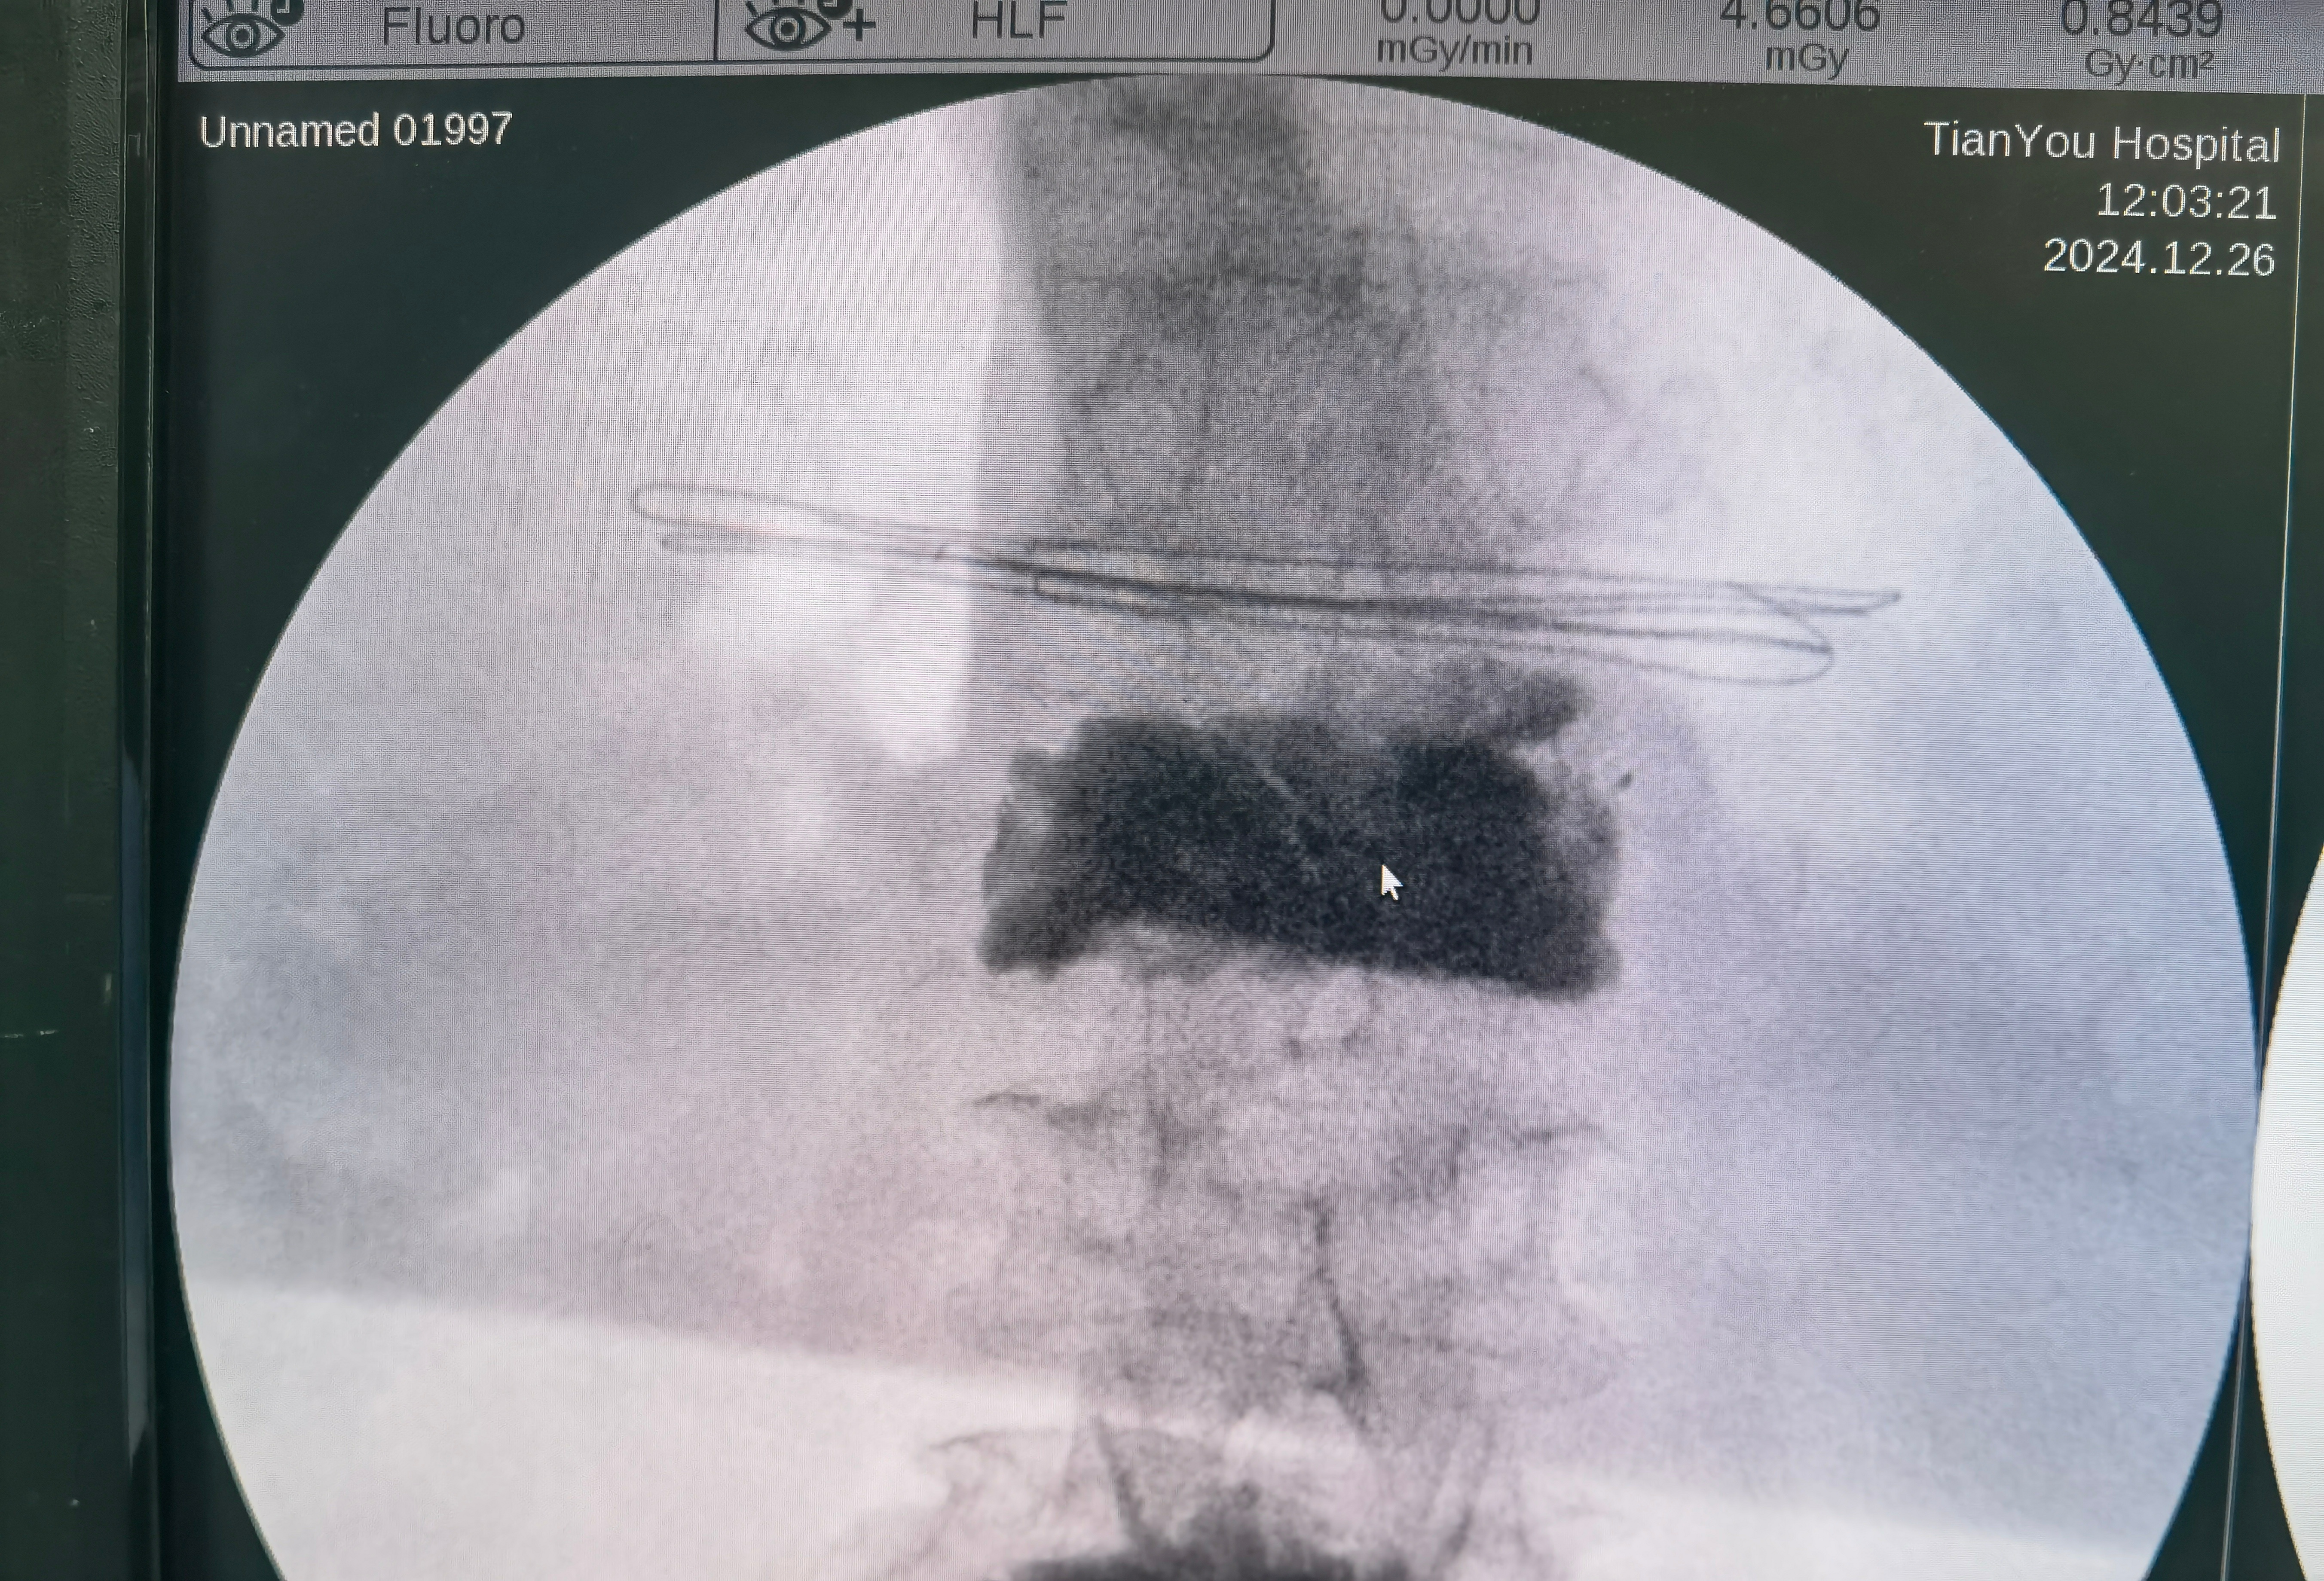

老人家的脊柱骨折首选微创手术,不建议保守治疗。看这个老太太,躺着做CT显示胸12椎体高度可,但是骨头里面有一个很大的空洞。站着拍片子这个椎体明显变矮了。这就是很恐怖的一种不稳定脊柱骨折。我们局麻注射骨水泥,注射了将近20毫升,这是极限操作,目的是把大空洞完全填满,把骨头撑起来,消灭不稳定。如果稍微少填一点,可能手术后还是不稳定,就会再骨折。这种极限操作的风险是很高的,水泥有可能漏到神经周围,导致病人瘫痪。所以大部分医生会选择做大手术,钉棒固定。